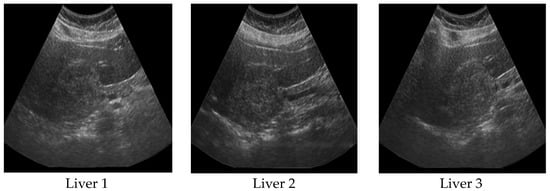

Figure 5 shows the variations when the axial resolution m is increased in radial-polar sampling, keeping the lateral resolution fixed at n = 40. The interpolation used was Lanczos-3 [19]. As the number of sampling points along axial beams is increased, we observe that the sector image becomes smoother and less grainy. When the value of m is kept increasing with a fixed value for n, the overall clarity of features diminish because of close proximity of sampling points. Therefore, we need to carefully select the values of m and n to obtain the quality of real ultrasound images.

Figure 5. Effect of changing axial resolution (m) in radial-polar sampling ([13], reproduced with permission).